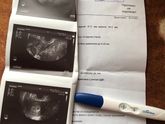

На сколько опасен ,тонус на задней стенке матки ????живу в Одинцово ,в свой выходной пошла на платное узи,срок 3 недели 3 дня .запись к врачу на 11 число … Читать далее